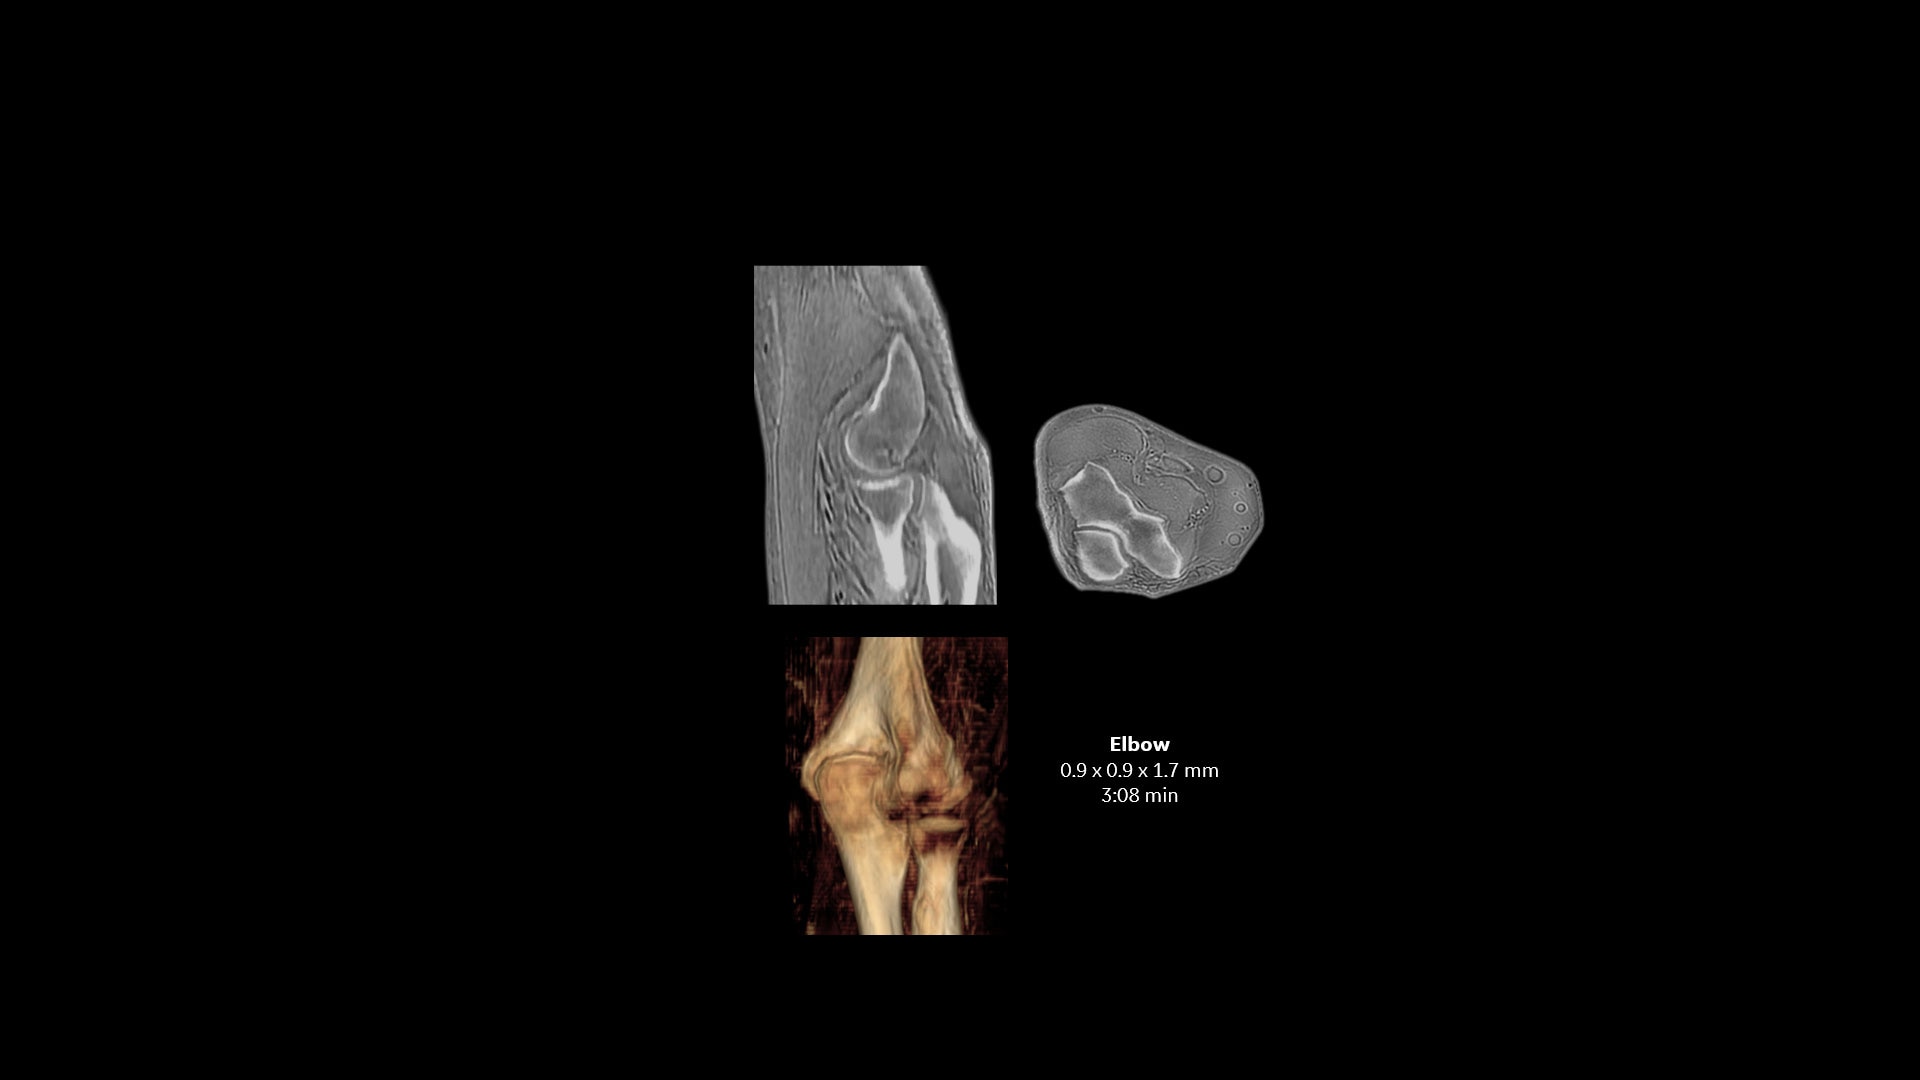

oZTEo ist für alle Anatomien ohne ionisierende Strahlung verfügbar und liefert dabei Bilder von Knochenmorphologie, Verkalkungen, Verknöcherungen und Frakturen. OZTEo ergänzt die herkömmliche MRT-Weichteilgewebeuntersuchung mit perfekter Anpassung und bietet isotropische 3D-Bildgebung unter Verwendung einer radialen ZTE-Erfassung (Zero TE) mit inhärenter Unempfindlichkeit bei Bewegungen. Verwendung von oZTEo mit Volumenbeleuchtung für realistisches 3D-Rendering.

Wenn oZTEo in eine MRT-Untersuchung einbezogen wird, werden Kortikalisknochendaten perfekt zusammen mit den Weichteilgewebsserien registriert, was sie zu einer zentralen Bildgebungsserie für die meisten routinemäßigen MSK-Anforderungen macht.

Mit dieser neuen Anwendung zur Darstellung von kortikalen Knochenoberflächen, basierend auf der radialen ZTE-Anwendung, können Sie eine neue Möglichkeit für die Knochenbildgebung anbieten und einen erheblichen klinischen Nutzen für Ihre orthopädischen Untersuchungen gewinnen.